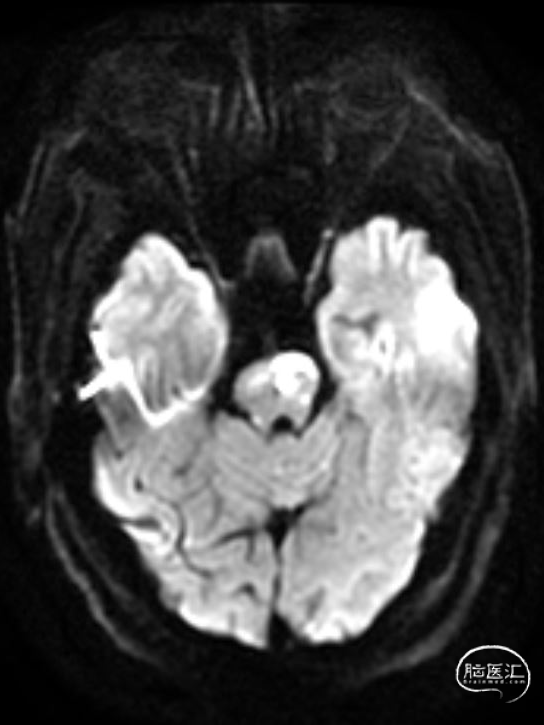

➢2023年11月06日

头颅MRI平扫:脑桥、左侧中脑、左侧桥臂急性脑梗死。